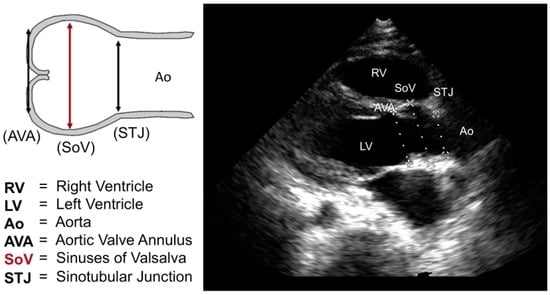

| AVA | Aortic valve annulus |

| SoV | Sinuses of valsalva |

| STJ | Sinotubular junction |